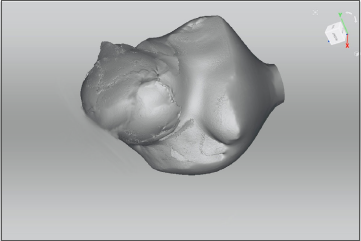

All patients underwent pre-operative volumetric analysis using both CT Angiography and 3D scanner. Post-operatively reconstructed breast volumes were measured using 3D scanner between 3-6 months. Breast volume on CT was measured by manually selecting the breast contour (Region of Interest, ROI) on each axial slice (Fig. 1). These ROIs were stacked to create a 3D reconstruction of the breast (Fig. 2). Hemiabdomen volume was measured on CTA from the anterior axillary line on the side of flap harvest, extending contralaterally up to the medial extent of the dominant perforator. This ROI corresponded to the anticipated DIEP flap territory based on perforator location and vascular dominance. Volume was then automatically calculated using Syringo.via software based on the cumulative ROI data(Fig. 3).

Figure 2. ROIs stacked to create a 3D reconstruction of the breast and the volume of the breast.